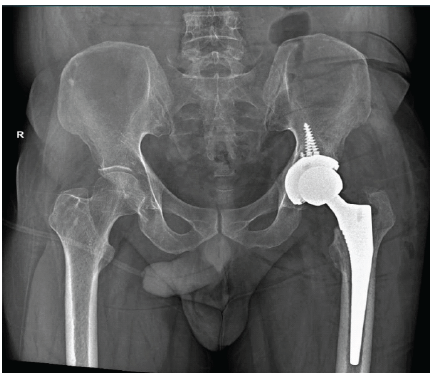

Atraumatic Subtrochanteric Stress Fracture in a 45-Year-Old Housewife: Diagnostic Challenge and Management Strategy

Gagandeep Gupta , Abhishek Singh , Shivang Kala , Akhilesh Saini , Shristi Singh , Abhijeet Sandhu

………………………………p.180-184